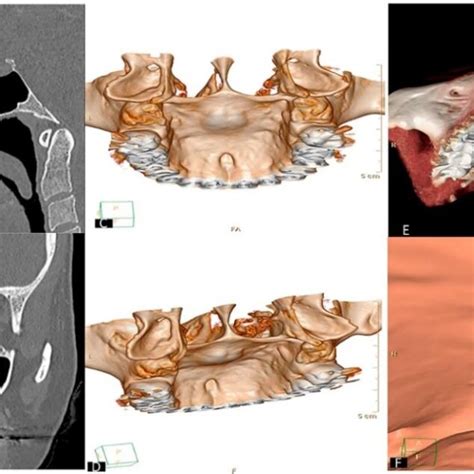

- Dientes supernumerarios (hiperdoncia): aunque suene extraño, a veces un “bulto” duro en el paladar puede ser en realidad un diente de más que está erupcionando en un lugar inusual. Por ejemplo, existen casos de incisivos extra (mesiodens) que aparecen en el paladar detrás de los dos frontales, o de muelas adicionales. Estos dientes extras pueden sentirse como protuberancias óseas.

- Quiste nasopalatino: es un quiste que se forma en el conducto nasopalatino (cerca de los incisivos centrales superiores). Cuando crece, puede abultar el paladar anterior con una hinchazón lisa.

- Pruebas complementarias: Dependiendo de lo que sospeche, puedo solicitar una radiografía (por ejemplo, una radiografía periapical o panorámica si sospecho de un origen dental o un diente extra), o incluso una biopsia.